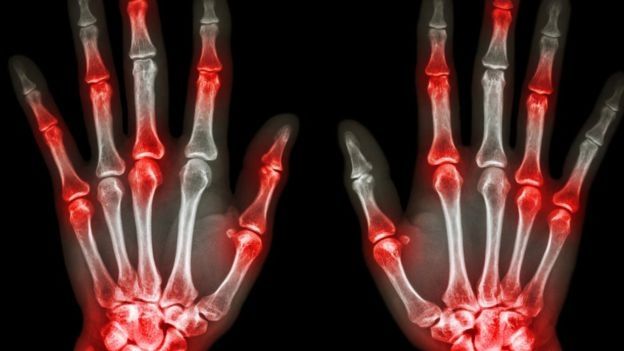

Un análisis de sangre que determine una velocidad elevada de la proteína C reactiva puede ser indicio de un proceso inflamatorio en el cuerpo, pero sigue sin ser un marcador específico de la artritis reumatoide.

La investigación fue llevada a cabocon 82 pacientes, de los cuales 51 no presentaban ningún síntoma y 31 padecían artritis reumatoide.

Del estudio se excluyó a los pacientes con otras condiciones como la diabetes melitus, enfermedad arterial periférica y neuropatías por la probabilidad de emitir una temperatura que alterara el experimento.

"El objetivo del estudio era determinar si los pacientes enfermos pero sin síntomas de inflamación o dolor tenían diferentes patrones termográficos en comparación con los sanos", dice el reporte.

Afirman que es el primer estudio en realizar esta comparación y que los resultados mostraron claramente que en este caso, las manos de los pacientes con síntomas tenían temperaturas superiores a las de los individuos sanos.

"Para la temperatura de la palma de la mano, las dos curvas de probabilidad (sanos y con la condición) se cruzaban en los 31,5 °C, lo cual implica que aquellos con temperatura inferior a esa eran más propensos a estar sanos, mientras que las personas cuya temperatura de la palma de la mano excedía los 31,5 °C eran más susceptibles de padecer artritis reumatoide", concluyó el estudio.

De forma similar, se midió también la temperatura de los dedos, y en ese caso el punto de cruce fueron los 30,3 °C, determinando así la frontera entre la probabilidad o no de tener artritis.

Los autores del estudio señalan cómo la termografía puede detectar signos de la enfermedad con mayor rapidez que otras modalidades similares. En concreto, comparan los resultados con pruebas de ultrasonidos, que no percibieron señales de artritis en la misma muestra experimental de pacientes.